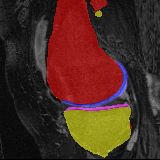

Knee MRI experiment: We test our method on 3D knee MRIs from the Osteoarthritis Initiative (OAI) 111https://nda.nih.gov/oai/ and corresponding segmentations of femur and tibia as well as femoral and tibial cartilage [1]. From a total of 507 labeled images, we use 200 for training, 53 for validation, and 254 for testing. To test registration performance we use 10,000 random image pairs from the test set. All images are affinely registered to an atlas built from the training images, resampled to isotropic spacing of 1mm, cropped to and intensity normalized to [0,1]. In addition, right knee images are flipped to be consistent with left knees. For training, the loss weights are , , and based on approximate hyper-parameter tuning. Note that when computing from the displacements, the image coordinates are scaled to [-1, 1] for each dimension following the convention in the interpolation function of PyTorch.

Results: All trained networks are evaluated using Dice overlap scores between predictions and the manual segmentations for the segmentation network, or between the warped moving segmentations and the target segmentations for the registration network. Tabs. 1 and 2 show results for the knee and brain MRI experiments respectively in Dice scores (%). Fig. 2 shows examples of knee MRI registrations and brain MRI segmentations.

Knee results: On knee MRIs, our method improves segmentation scores over separately learned networks by about 1.2 and 0.5, and registration scores increase by about 3.1 and 3.0, when training with 5 and 10 manual segmentation respectively. Especially for the challenging cartilage structures, our joint learning boosts segmentation by 1.4 and 0.7, and registration by 5.5 and 5.2 for N=5 and N=10 respectively.

Qualitative results: DA achieves more anatomically consistent registrations than the mono-networks on the knee (Fig. 2) and Brain MRI samples (see supplementary material).